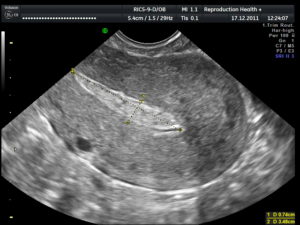

Гинеколог выявляет мягкую консистенцию органа при осмотре. Подтверждают развившийся негативный процесс клинические и биохимические анализы мочи и крови, трансвагинальное УЗИ (ультразвуковое исследование).

Проводится визуальный осмотр шейки матки и пальпация. Внутренний зев ее будет расширен, плодный остаток в наличии. УЗИ определит его объем и локализацию, а также общее состояние репродуктивных органов. Биохимический анализ крови расскажет о функционировании органов и систем пациентки.

При неполном аборте беременность больше не подтверждается различными тестами, поэтому примерно через неделю после отторжения плодного яйца необходимо сделать УЗИ, чтобы удостовериться, что в матке нет остатков эмбриональной ткани. Если остатки плодного яйца после медикаментозного прерывания беременности обнаружены, следует вовремя начать лечение.

Послеоперационное лечение обычно заключается в том, что проводится обследование гормонального фона, а также назначается антибактериальная терапия. Нужны регулярные контрольные гинекологические осмотры – берутся мазки на микрофлору и назначается УЗИ органов малого таза.

Что делать? Лучше этот вопрос заранее обговорить с врачом. По стандартным рекомендациям УЗ-исследование после аборта выполняют на 10-14 день, но если это сделать через 5-7 дней, то есть возможность вовремя заметить признаки неполного аборта и назначить лекарственные средства.

Через 2–3 дня женщина вновь должна посетить врача. Гинеколог осмотрит пациентку, оценит ее состояние. Будет проведено УЗИ, результат которого покажет эффективность проведенной процедуры. Если выкидыш при помощи медикаментозных средств не произошел, женщине понадобится чистка. Беременность после фармаборта сохранять нельзя.

При появлении первых симптомов, вызывающих опасение, женщина должна обратиться в больницу. Основными методами диагностики состояния являются гинекологический осмотр и УЗИ.